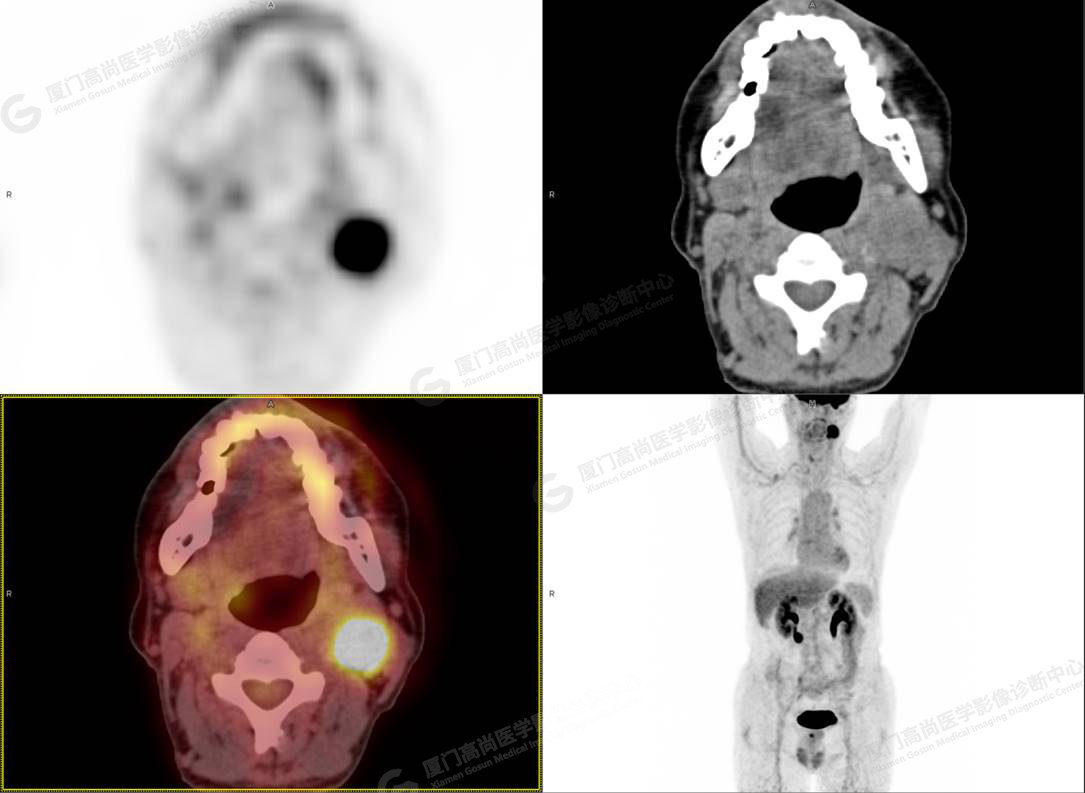

PET/CT影像圖

圖4

PET/CT所見:左側頸部(II區(qū))見腫大淋巴結,大小約2.5cm×2.3cm,其內密度不均,邊界尚清,放射性攝取異常增高,早期SUVmax 11.5,延時SUVmax 14.5。

影像診斷: 左側頸部(II區(qū))腫大淋巴結,代謝異常增高,考慮腫瘤性病變可能性大(淋巴瘤?轉移瘤?),建議病理學檢查明確。

病理診斷:(左頸部結節(jié))副神經節(jié)瘤。